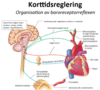

Hur hålls MAP konstant (övergripande) och varför är det viktigt?

- Det kardiovaskulära systemet behöver hålla MAP konstant och tillräckligt högt för att säkerställa glomerulär filtration

- I princip modifieras funktionen hos hjärta, artärer, vener och medulla

- Varje organ reglerar också lokalt blodflödet genom att minska eller öka resistens i lokala arterioler

Var sitter högtrycksbaroreceptorerna och hur fungerar dem?

Aortabågen och sinus caroticus

Mäter av “trycket”

- Fungerar genom mekanoreceptorer (TRPC-kanalerna själva) som reagerar på sträckning (egentligen inte transmuralt tryck)

- Vilket leder till att TRPC-kanaler öppnas och inströmning av Ca2+ och Na+ och aktionspotentialà information går via nervus glossopharyngeus (sinus caroticus) och nervus vagus (aortabågen) till medulla via efferenta banor tillbaka till exempelvis hjärta och kärl

Vad blir effekten av baroreceptorernas signalering vid högt tryck?

Högt tryck

- Afferenta neuron går till medulla oblongata som kopplar till NTS (nucleus tractus solitarii) i medulla (medullärt kardiovaskulärt center)

- Vasodilatation i systemartärer (hämning av sympatikus)

- Bradykardi (parasympatiskt)

- Mindre frekvens och kontraktilitet hjärta (hämning av sympatikus)

- Vagusnerven genom acetylkolin till M2-R och ger sänkt hjärtfrekvens, långsammare AVN överledning, påverkar inte kontraktiliteten nämnvärt

Sammantaget minskar sympatiskt påslag vilket ger lägre slagvolym och minskad frekvens av vasomotoriska impulser (kärldiameter ökar) i vissa kärl (t ex hud och tarm), sammantaget ger detta ett lägre tryck

Hur kan stress trigga innervering?

- Innervering kan ske direkt från cerebrala cortex, limbiska systemet och hypothalamus ex vid stress vilket då kan koppla kardiovaskulära centra i medulla oblongata och aktivera vasomotorområdet och kardioacceleratoriska området med samma typ av effekter som ska ske vid lågt blodtryck